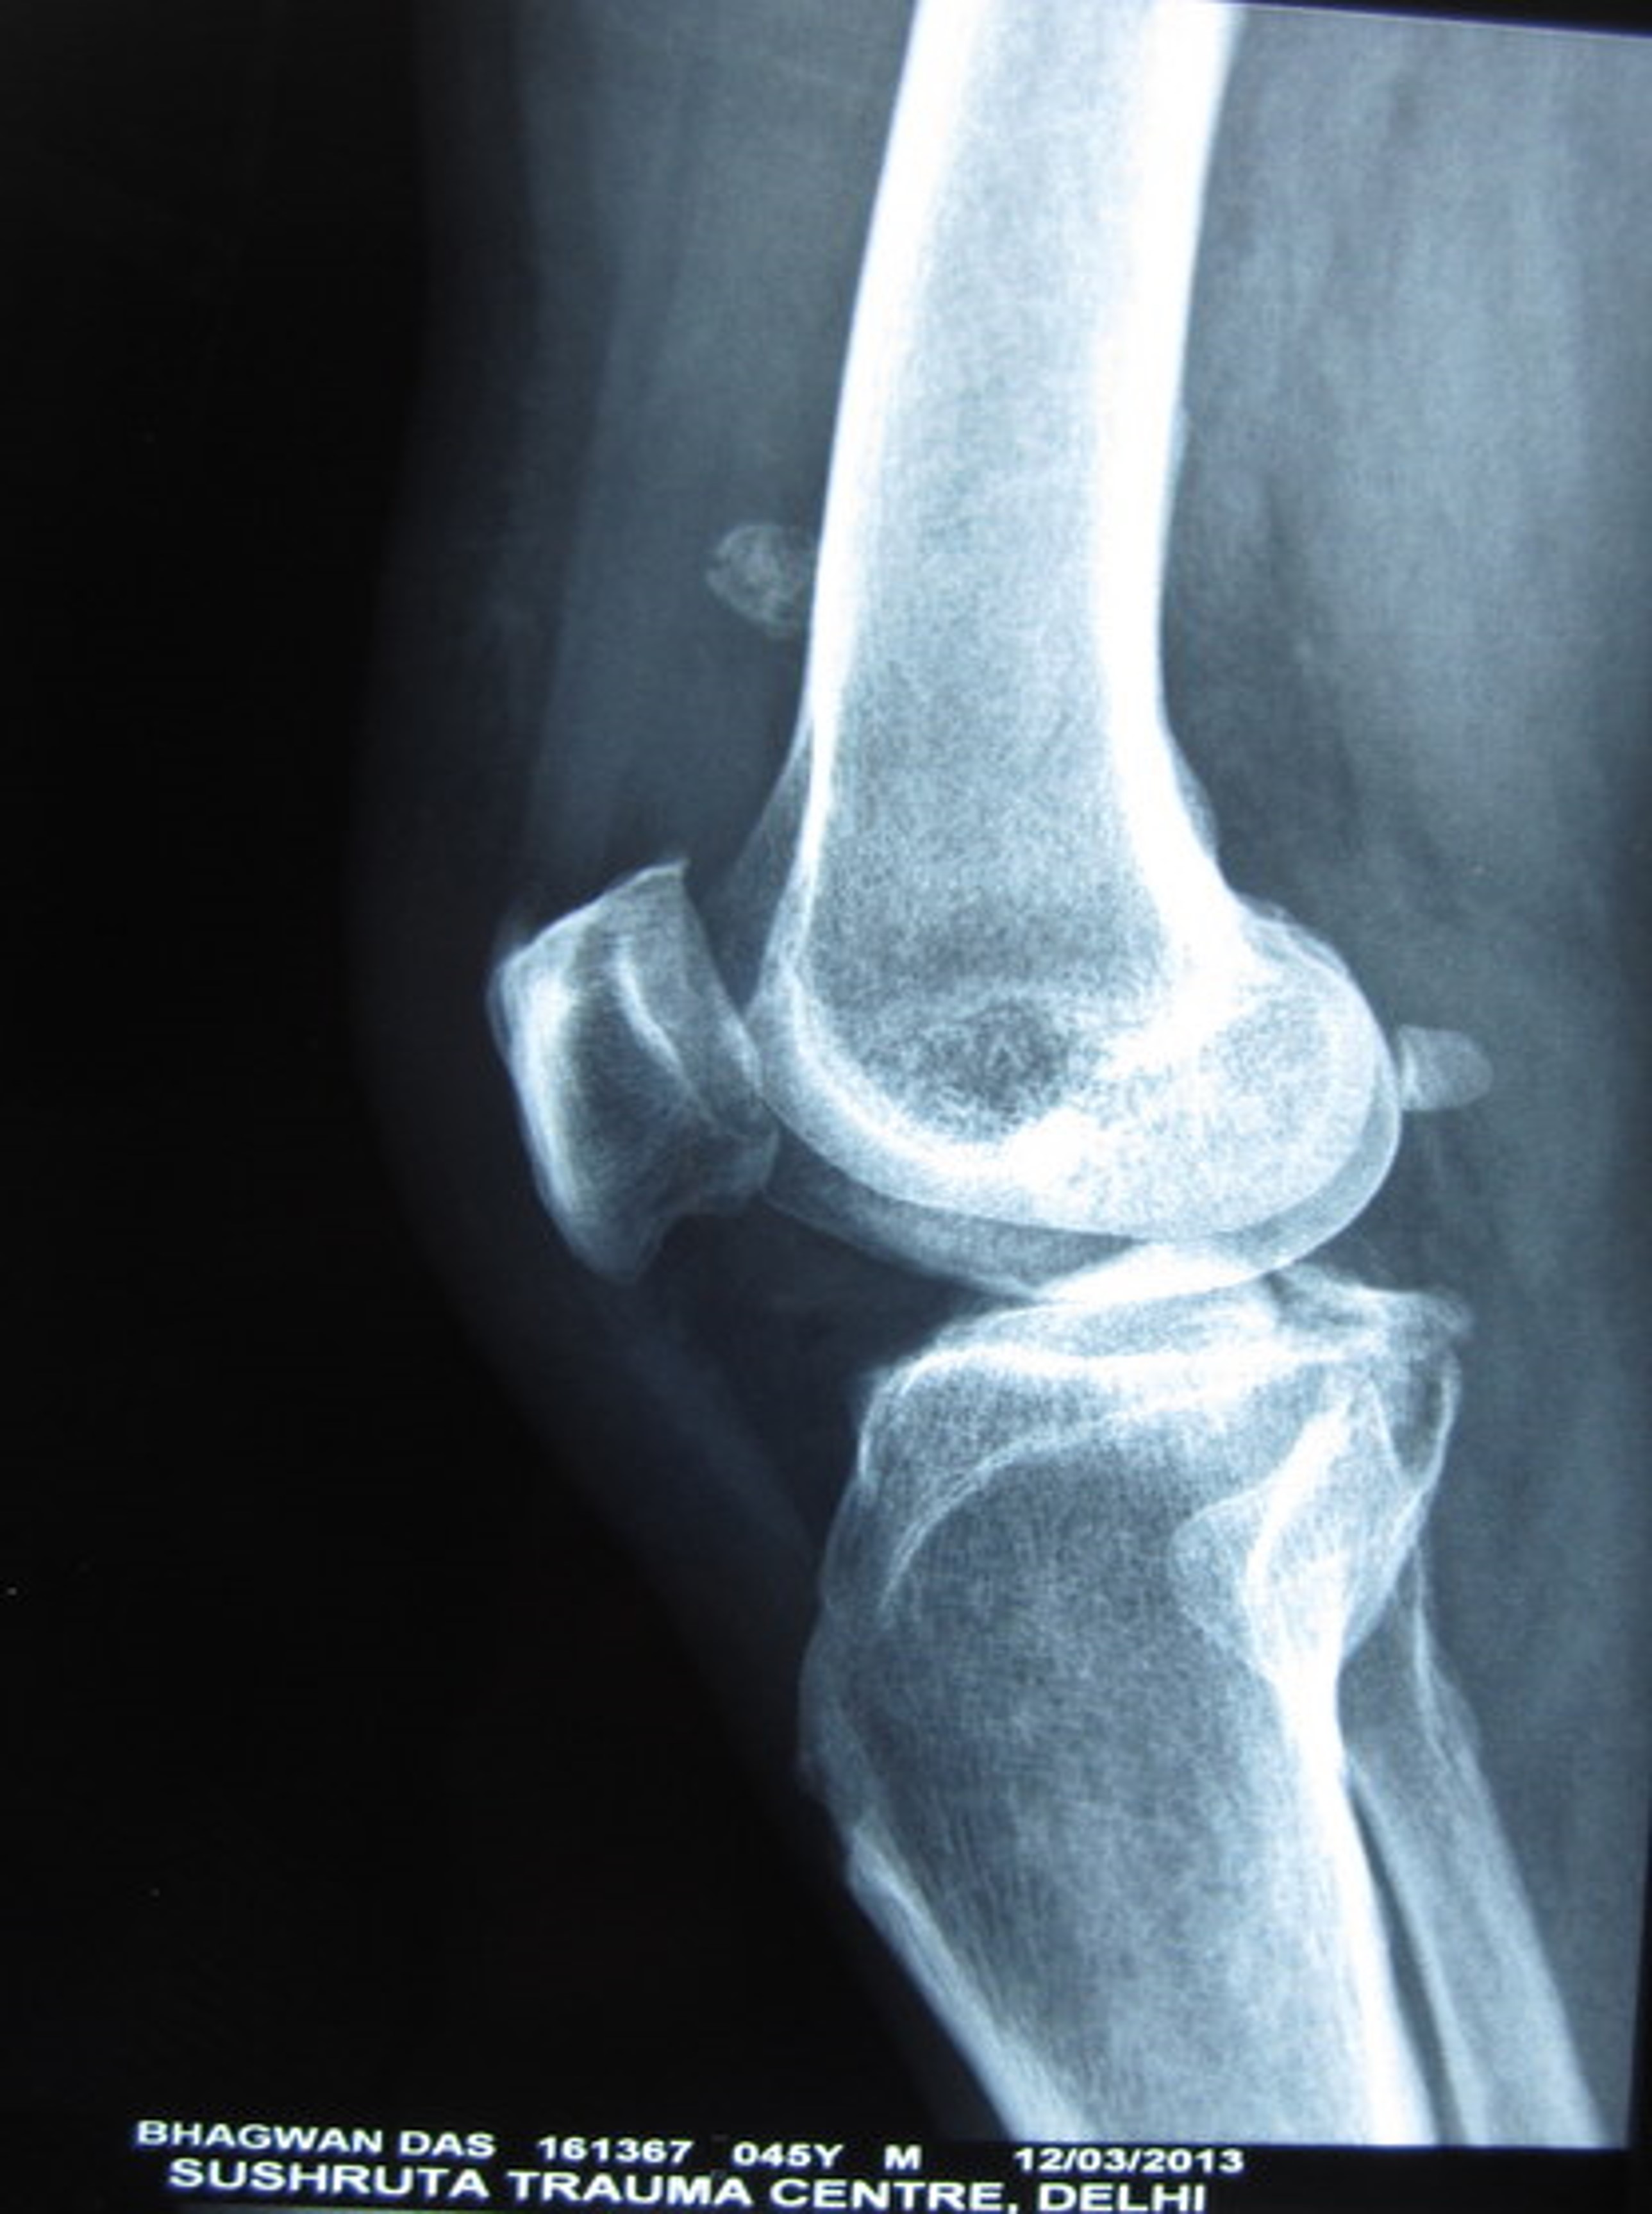

Case 1 pre op xrays and post op xrays